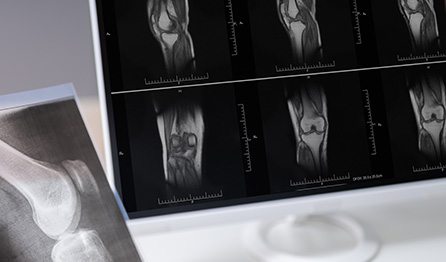

골 연령 검사

골 연령이 자신의 나이와 맞는지

검사하는 것이 골연령 검사라고 하고,

흔히 성장판 검사라고 합니다.